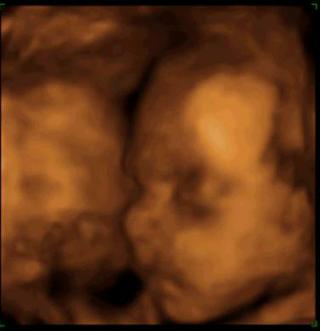

@lebo5 v utorok sme boli na utz ale este nemame srdiecko kontrolne sono mame 22.10.prikladam foto nasej bublinky

@10andrea12 krasna bublinka

@10andrea12 veru krásna - pre vás tá najkrajšia - držím palce

moja bublinka už je troška väčšia